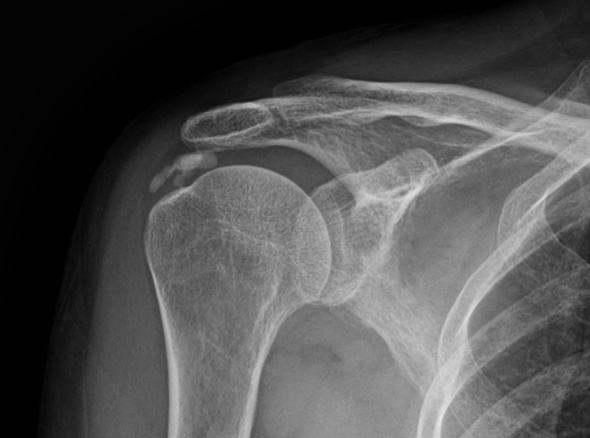

어깨 힘줄 내부에 칼슘 석회가 침착되어 힘줄의 손상과 함께 통증을 유발하는 질환입니다.

석회화건염은 외상으로 인해서 발생하는 것과 무관합니다.

주로 40대 연령층에서 흔하게 발생하는 질환입니다.

석회화건염은 어깨 질환중 갑작스럽게 통증이 나타나는 경우가 많이 있습니다.

어깨 속에 석회가루가 쌓여 통증을 유발하는 석회화건염은

석회는 신체 어느 부위에서나 발생할 수 있으나 어깨에 가장 많이 발생합니다.